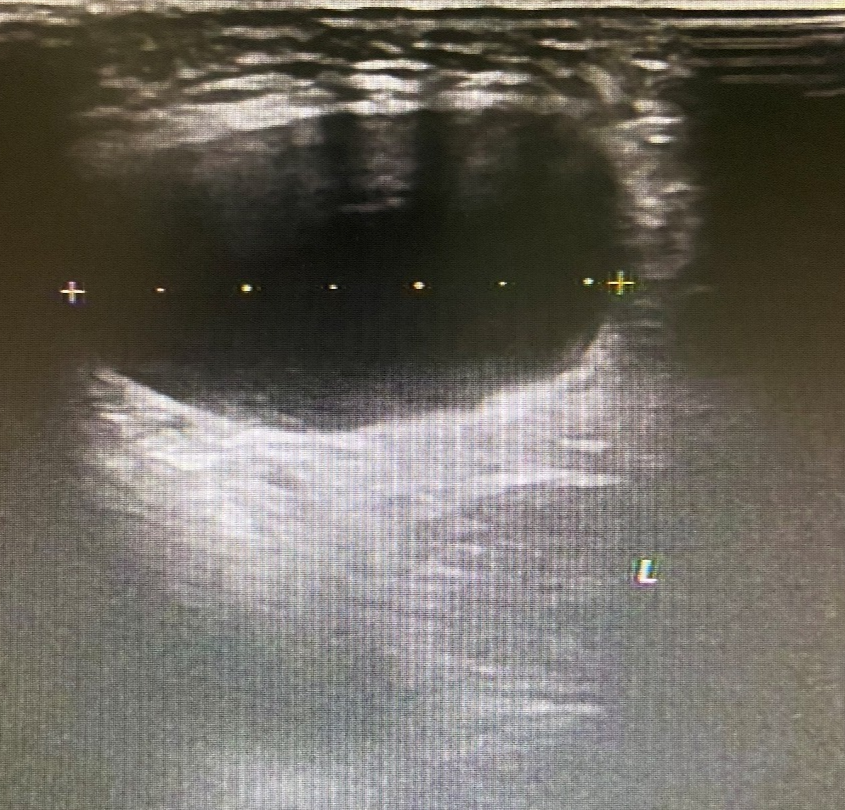

图 2 左侧腹股沟区包块

超声所见

左侧腹股沟区见范围约 4.4cm×3.2cm×2.0cm 无回声区,可见少量分隔,增减腹压大小无明显变化。右侧腹股沟区未见明显异常回声。

超声提示

左侧腹股沟无回声区,子宫圆韧带囊肿?积液?

术后证实为左侧子宫圆韧带囊肿。